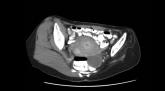

ArticleAsymmetric muscle atrophy from childhood polioAuthor:Lailey Sooriash, MDPublish date: December 14, 2007Read More